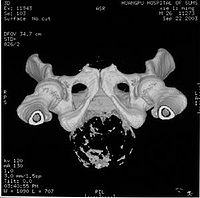

3.CT检查 CT对确定肿瘤具有定位和定性价值,发现肿瘤有钙化或斑块形成,具有重要价值,并可指导手术静脉注药后能够明显强化,有助于阐明肿瘤的内容物及其周边包膜特征骶骨脊索瘤的骨扫描检查常为密度减低或冷结节检查时要除外重叠的膀胱阴影,为此检查前应使膀胱排空或做侧位扫描。CT可清晰显示脊索瘤骨破坏和软组织阴影与马尾神经、大血管及周围组织的关系注射造影剂可增强CT影像的清晰度。据文献报道脊索瘤的囊性变可在CT中有斑点状和低密度区表现;血管造影对颈椎脊索瘤的诊断有帮助;脊髓造影可显示肿瘤在硬膜外扩展在椎管内的生长可超越骨质破坏范围对手术方案的制定有帮助。